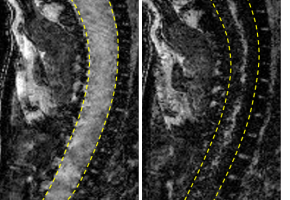

Mercredi 31 mai, se tiendra la Journée mondiale de la sclérose en plaque (SEP), l’occasion pour les associations d’appeler à la mobilisation pour cette maladie neurodégénérative qui touche 100 000 personnes en France et constitue la 1ère cause de handicap non traumatique chez l’adulte jeune. Malgré une évolution en forte progression ces 10 dernières années (4000 nouveaux diagnostics annuels), la maladie reste peu connue, entrainant une errance diagnostic, qui est de 5 ans aujourd’hui. Les associations, et en particulier l’Association française des sclérosés en plaques (Afsep) réclament donc l’obtention du statut de grande cause nationale 2018 et le développement de campagnes d’information et de communication sur ce sujet auprès du grand public. A l’heure actuelle, l’imagerie IRM est largement utilisée pour le diagnostic et le suivi des patients atteints de SEP. Mais des chercheurs français (équipe « SpPrIng » dirigée par Fabian Docagne au sein de l’unité Inserm U1237 de Caen) ont voulu aller plus loin et se sont demandés si cet examen pourrait permettre de prédire l’apparition des poussées. Pour cela, ils ont développé une méthode d’IRM qui permet de suivre dans l’espace et dans le temps l’évolution de la maladie. Elle est basée sur le fait que la sclérose en plaques est due, au moins en partie, au passage de cellules inflammatoires (lymphocytes notamment) dans le cerveau et la moelle épinière à travers la paroi des vaisseaux. Pour pouvoir traverser, les cellules se fixent à des molécules d’adhésion présentes à la surface de vaisseaux sanguins. Les chercheurs ont donc eu l’idée de suivre l’évolution de billes de fer détectables par IRM se fixant sur ces molécules d’adhésion. Ils ont testé cet outil sur des souris présentant un modèle de sclérose en plaques. Dans leur étude, publiée dans la revue Pnas, ils ont montré que l’IRM révèle le passage des cellules inflammatoires et permet ainsi de prédire la survenue d’une poussée chez les souris asymptomatiques et les rémissions chez des souris malades. Les billes de fer sont visualisées en noir, dans la moelle épinière, révélant ainsi une inflammation. "Cette technique pourrait à l’avenir être adaptée chez l’homme pour améliorer le pronostic et le suivi de la maladie chez les patients atteints de sclérose en plaques", conclut l’Inserm.